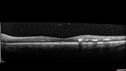

Macular ischemia left eye in type I diabetic (enlarged foveal avascular zone)213 views29 year old female with type I diabetes since age 5. Left eye has enlarged FAZ with vision of 20/20 OD and 20/60 OS. Both eyes have CSME. The left eye did have focal laserApr 12, 2023

Macular ischemia left eye in type I diabetic (enlarged foveal avascular zone)229 views29 year old female with type I diabetes since age 5. Left eye has enlarged FAZ with vision of 20/20 OD and 20/60 OS. Both eyes have CSME. The left eye did have focal laserApr 12, 2023

Macular ischemia left eye in type I diabetic (enlarged foveal avascular zone)216 views29 year old female with type I diabetes since age 5. Left eye has enlarged FAZ with vision of 20/20 OD and 20/60 OS. Both eyes have CSME. The left eye did have focal laserApr 12, 2023